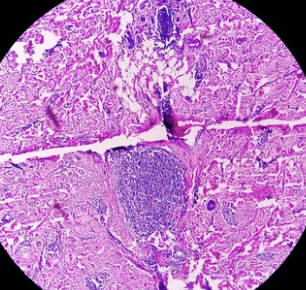

자궁내막암(Endometrial cancer)은 자궁 내막(Endometrium)에서 발생하는 암으로, 여성 생식기암 중 가장 흔한 유형입니다. 자궁내막암은 주로 폐경기 이후 여성에게 많이 발생하며, 비정상적인 질 출혈이 주요 증상으로 나타납니다.

2) 자궁내막 조직검사 (Endometrial biopsy)

- 자궁내막에서 조직 샘플을 채취하여 암세포 유무를 확인하는 검사.

- 통증이 거의 없으며, 비교적 간단한 검사 방법.